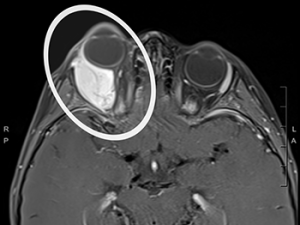

Colton Goodman of China Grove, North Carolina, was just 3 years old when he was referred to Duke after an MRI showed a growth behind his right eye. At Duke, he was diagnosed with rhabdomyosarcoma, a life-threatening muscle tissue cancer that is most often seen in children.

Image of the tumor behind Colton's eye.

The recommended treatment for this cancer is chemotherapy followed by surgery and/or radiation, but because the tumor’s location was not amenable to surgery, his doctor, Lars Wagner, MD, recommended chemotherapy and proton beam radiation. Proton therapy is a more precise type of radiation that has fewer side effects than conventional radiation therapy.

Because proton therapy is more precise, it can be better directed and controlled so that the bulk of radiation is delivered to the tumor, sparing healthy tissue. This is especially important for children and for tumors located in sensitive areas like the head and neck.